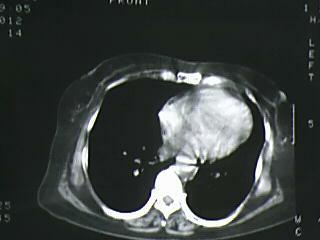

以下是引用杀毒软件在2009-4-14 17:52:00的发言:[br]考虑---右肺继发型肺结核---纵隔淋巴结多发钙化----左肺支扩

以下是引用黑白光影在2009-4-14 20:36:00的发言:[br]右肺继发型肺结核;左下慢性支气管炎性病变。